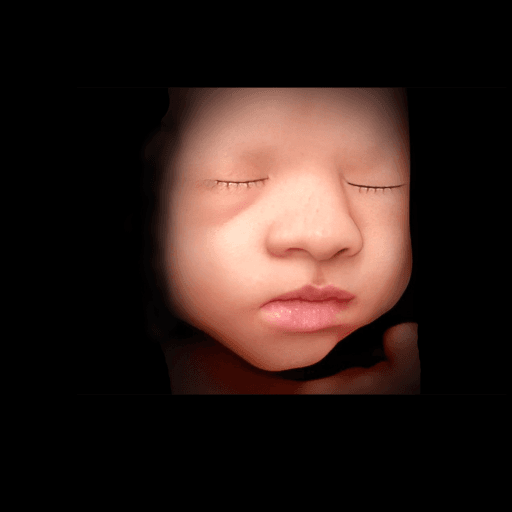

Simply upload your 3D ultrasound image and proceed from there. Our system will guide you through the enhancement process step by step.